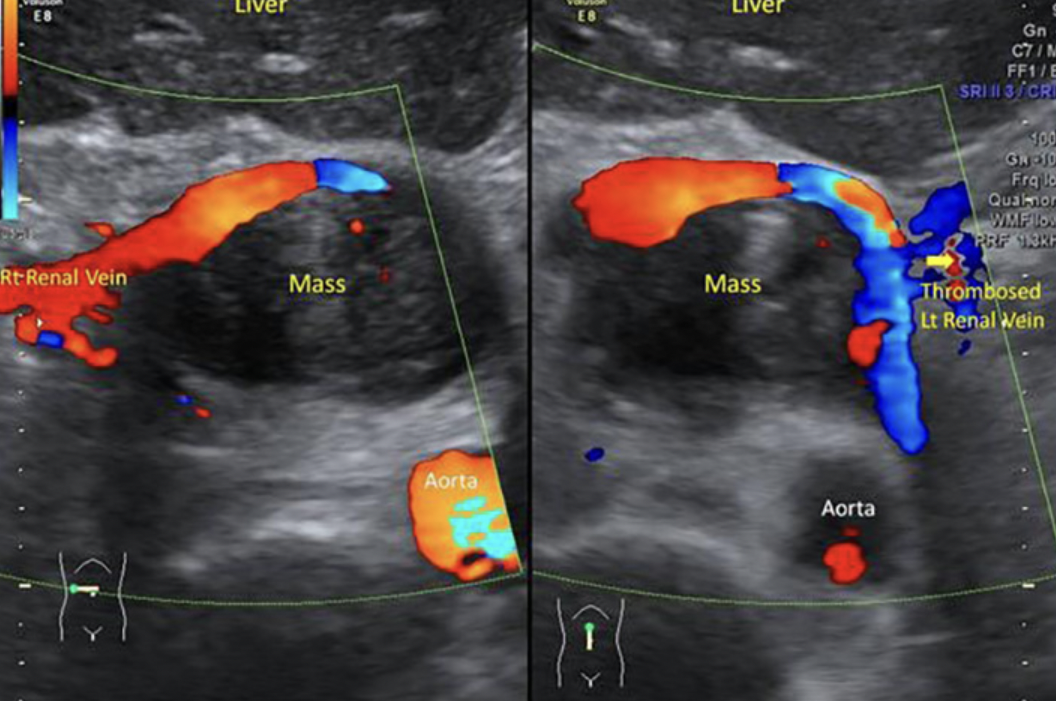

Quiz 2

Abdomen, Chest, Vascular

Case Number :Q-0002

2022-06-01

READ MORE